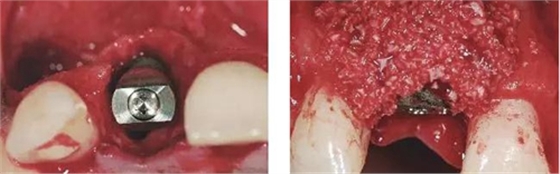

圖6、從磨牙后區(qū)用環(huán)形鉆獲取自體骨,并將其放置在種植體的表面。Geistlich Bio-Oss®骨顆?;旌涎悍胖迷谧泽w骨的外側,防止自體骨的早期吸收。植骨可以穩(wěn)定軟組織外形。

圖7、植骨區(qū)外覆蓋Geistlich Bio-Gide®雙層膠原膜,使得植骨區(qū)更為穩(wěn)定。